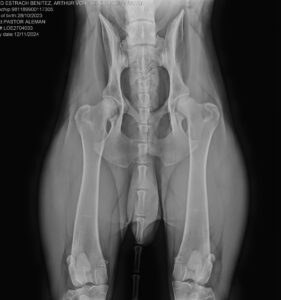

Ya tenemos los resultados de las radiografías oficiales de Arthur von der Eichberg-Ranch, nuestro futuro reproductor de las próximas CAMADAS H y I, programadas para …